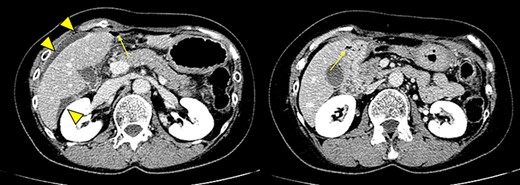

Our patient was a 59-year-old woman with past history of hysterectomy, bilateral salpingo-oophorectomy, regional lymphadenectomy and omentectomy performed for advanced ovarian cancer 3 years prior. She was experiencing abdominal pain over the past 2 days and visited our hospital owing to pain exacerbation. Contrast-enhanced abdominal computed tomography showed free air with ascites around the liver and duodenum perforation (Fig. 1). Tenderness and muscular defense were found mainly in the upper abdomen. Her white blood cell count and C-reactive protein levels were 17 200/μl and 0.04 mg/dl, respectively. Our clinical diagnosis was duodenal perforation with peritonitis.

Contrast-enhanced abdominal computed tomography showing free air (arrow) and ascites (arrowhead) around the liver and duodenal perforation.